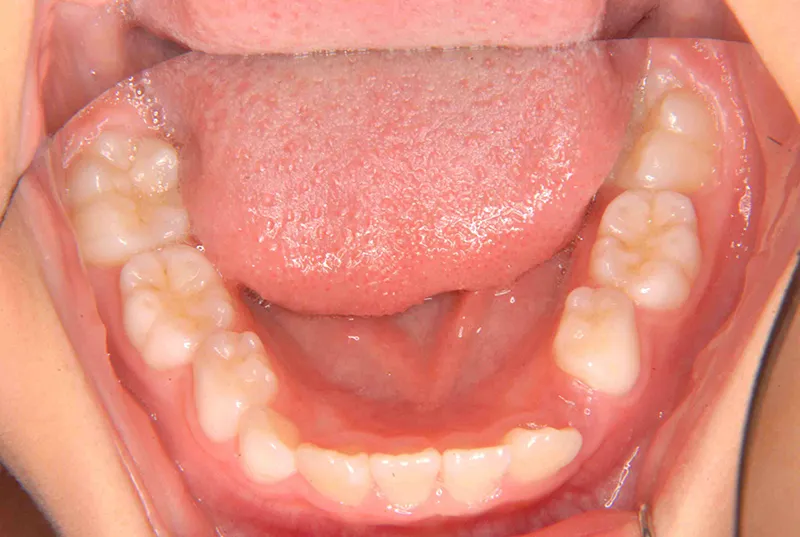

治療終了後

マルチブラケット装置は使わずに、最低限の必要な装置を使って目立たないように治療しました。

治療回数29回、2年10ヶ月の治療期間で矯正治療を終了しました。

主訴が改善され、ご満足頂きました。